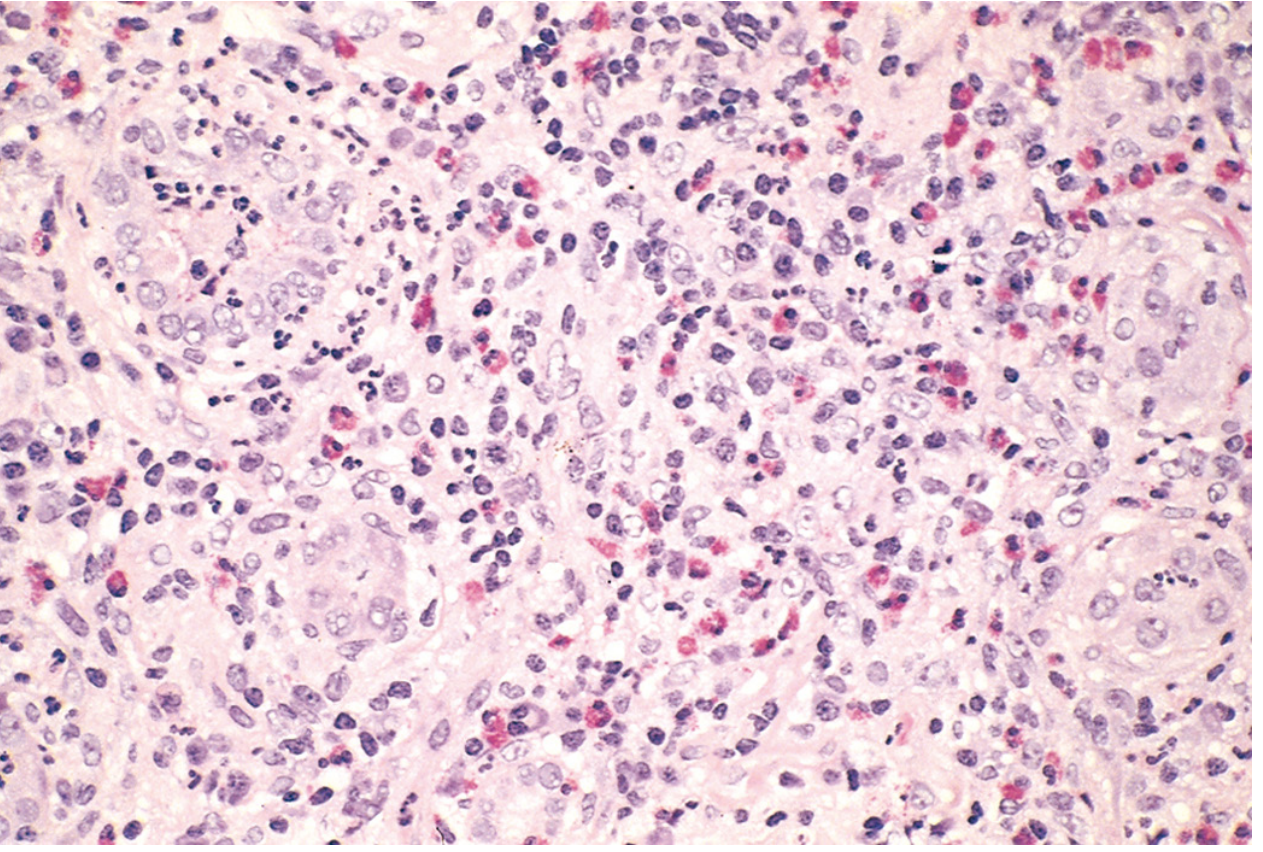

Renal biopsy — acute drug-induced interstitial nephritis. Dense interstitial infiltrate of lymphocytes, macrophages, eosinophils, and neutrophils with interstitial edema and tubular injury.

Histopathology findings:

• Interstitium: Pronounced edema with dense mononuclear infiltrate (lymphocytes, macrophages). Prominent eosinophils and neutrophils present in clusters.

• Tubules: Tubulitis (lymphocytic infiltration into tubular epithelium); variable tubular injury and early regenerative changes.

• Glomeruli: Normal morphology (no glomerulonephritis).

• Vessels: No vasculitis.

• Granulomas: Absent in this case.